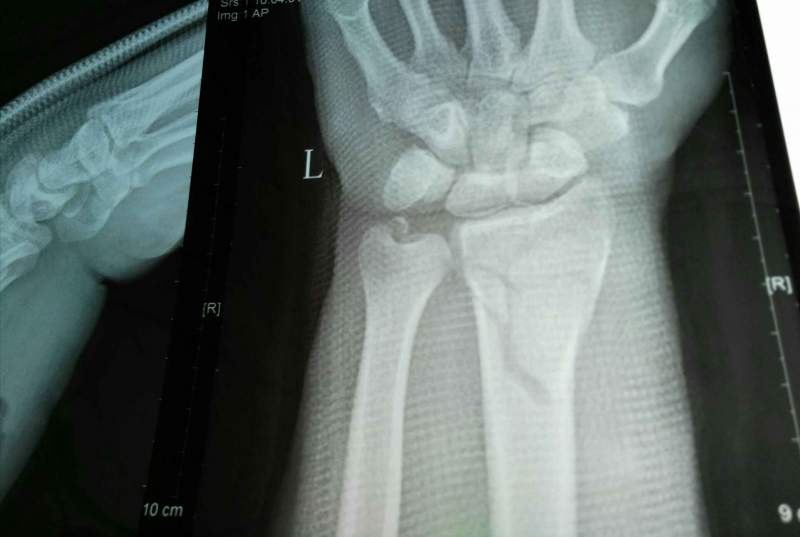

°Ö°Ö×óÊÖÍó¹ÇÕÛ£¬ÕâÊǸ´Î»Ö®ºóÅĵģ¬ÕâÔõôÑù£¿ ÒÑÓÐ3È˲ÎÓë

| ¸´Î»Í¦ºÃÁË£¬ºÃºÃÑø×žÍÐУ¬Ê¯¸à¹Ì¶¨4-6ÖÜ |

¶Ôλ¶ÔÏß¶¼Í¦ºÃ£¬¹Ì¶¨6ÖÜ£¬¼ÓÇ¿ÓªÑø ·¢×ÔСľ³æAndroid¿Í»§¶Ë |

û×öÊÖÊõ£¬ÊÖ·¨¸´Î»£¬Õâ¾ÍºÜºÃÁË¡£ ·¢×ÔСľ³æAndroid¿Í»§¶Ë |